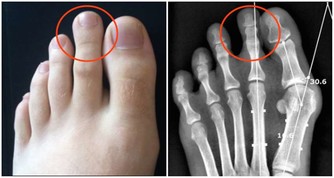

除了廚房裡面的食用調料容易產生黃曲霉毒素,還要注意食用的餐具也是很容易會被污染。例如就是小筷子,時間一長了,就會有出現裂縫和小毛刺之類的東西,如果清洗不干淨,難免會有一些殘留物在筷子的上面,這樣子食物就會逐漸地發霉,這樣子的情況下就特別容易會滋生黃曲霉毒素。長期下來,對肝臟的健康造成一定的威脅,大大是加重肝病的發病率。